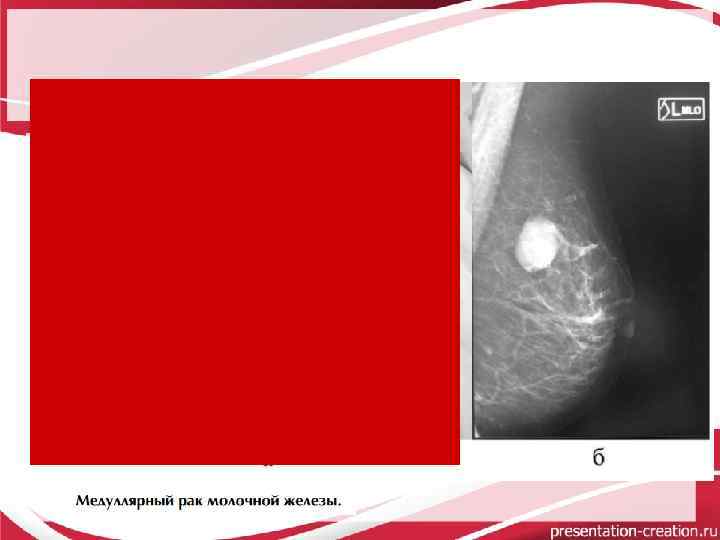

Медуллярный РМЖ

Медуллярный, папиллярный, слизистый и метапластический - постановка диагноза затруднена, поскольку данные маммографии и УЗИ зачастую соответствуют картине доброкачественного образования: опухоли имеют четкие округлые контуры, однородную структуру и небольшой размер, а при трепанобиопсии часто получают материал из участка фибросклероза, лимфоидные элементы, пролиферирующий кубический эпителий.